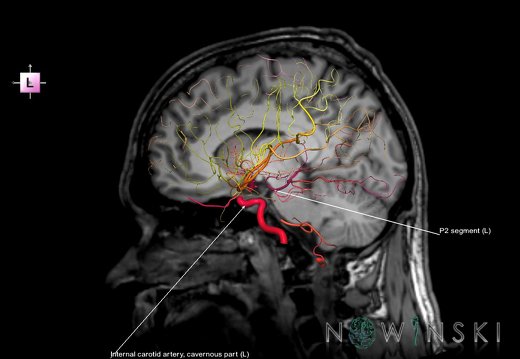

G6.T15.2.V2.P30S.Intracranial arteries–Triplanar